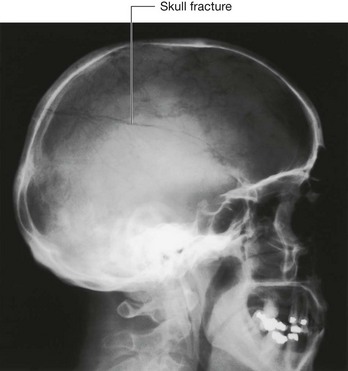

In the clinic

Medical imaging of the head

Radiography

Until two decades ago the standard method of imaging the head was plain radiography. The radiographs are taken in three standard projections—namely the posteroanterior view, the lateral view, and the Towne’s view. Additional views are obtained to assess the foramina at the base of the skull and the facial bones. Currently, skull radiographs are used in cases of trauma, but such use is declining. Skull fractures are relatively easily detected (Fig. 8.28). The patient is assessed and treatment is based upon the underlying neurological or potential neurological complications.

Fractures of the skull vault and extradural hematoma

The skull vault is a remarkably strong structure—and quite rightly, because it protects our most vital organ, the brain. The shape of the skull vault is of critical importance and its biomechanics prevent fracture. From a clinical standpoint skull fractures alert clinicians to the nature and force of an injury and potential complications. The fracture itself is usually of little consequence (unlike, say, a fracture of the tibia). Of key importance is the need to minimize the extent of primary brain injury and to treat potential secondary complications, rather than focusing on the skull fracture. Skull fractures that have particular significance include depressed skull fractures, compound fractures, and pterion fractures.

Pterion fractures

The pterion is an important clinical point on the lateral aspect of the skull. To find the precise point of the pterion, an imaginary line 1 inch (2.5 cm) above the zygomatic arch, and 1 inch (2.5 cm) posterior to the lateral orbital margin will approximate to this region. At the pterion the frontal, parietal, greater wing of the sphenoid, and temporal bones come together. Importantly, deep to this structure is the middle meningeal artery. An injury to this point of the skull is extremely serious because damage to this vessel may produce a significant extradural hematoma, which can be fatal.